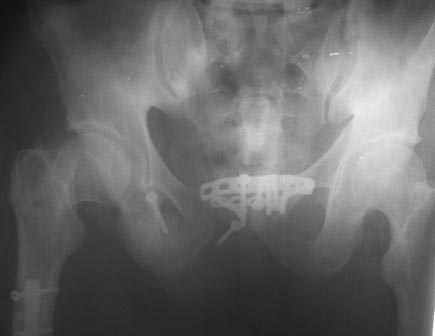

Ситуация типичная. При разрыве и соответственно несостоятельности крестцово-подвздошного сочленения изолированная фиксация лонного сочленения обречена на неудачу. В таких ситуациях целесообразно кроме пластины на лонное сочленение дополнительная фиксация либо таза в АВФ, либо крестцово-подвздошного сочленения винтами.

Это типичное осложнение, причиной которого является пренебрежение фиксации разорванного илеосакрального сочленения. Андрей Середа прав, что-то там с проксимальным отделом правого бедра не все благополучно, похоже есть базальный перелом. Наверно поэтому больной и правую ногу не нагружал? Нагружал левую половину таза с нефиксированным задним повреждением тазового кольца. Осложнение закономерно. Что делать? Реостеосинтез: спереди симфиз пластиной (или опять двумя), сзади илеосакральные винты слева (или с обеих сторон? СТ делали?). И с проксимальным отделом правого бедра разбираться...

На мой взгляд, никакой стандатной ошибки по нефиксированным задним отделам нет. Во всяком случае, выглядит это как APC II и фиксация сзади избыточна.

Проблема скорее случилась из-за некорректного остеосинтеза передних отделов. Рентгнологически щель лонного сочленения выглядит слишком узкой и сохраялось передне-заднее смещение, скорее всего - не хватило контакта, вот и разъехалось.

Действительно, ситуация несколько прояснилась, повреждение было APC III, необходимо было добавить IS винт. Сейчас: пластина с аппаратом или винтом.